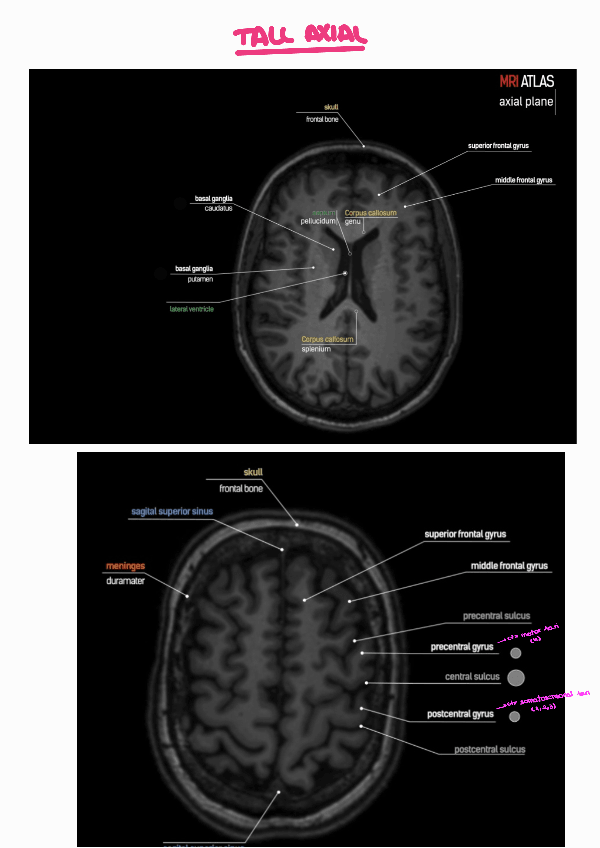

He publicado nuevos practicas de 3º Radiologia General: PRACTICA-3-RADIOLOGIA-1.pdf

3 páginas